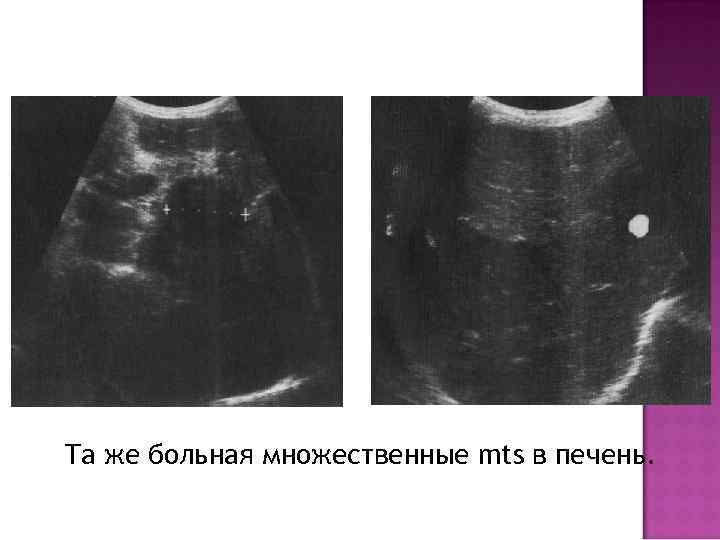

Та же больная множественные mts в печень.